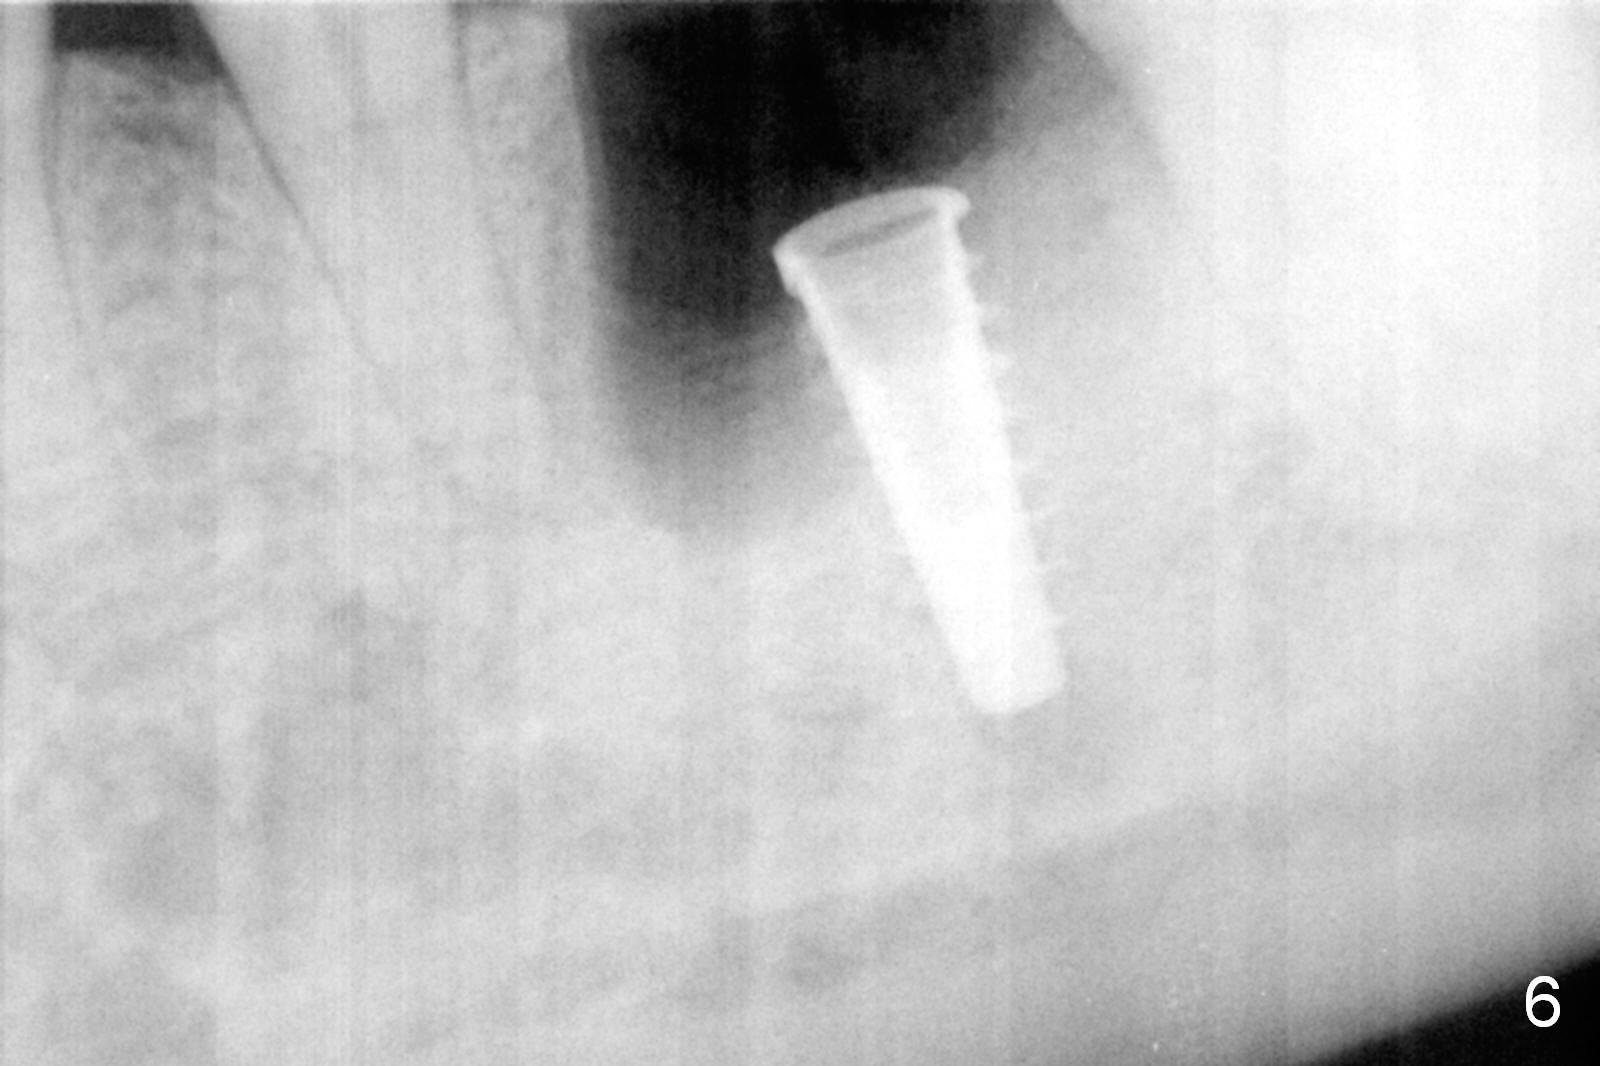

The asymptomatic tooth (#19) has a midbuccal fistula (Fig.1 <). The mesiobuccal pocket is 10 mm with purulent discharge from the sulcus (Fig.2,3). The mesiobuccal wall defect is confirmed when the tooth is extracted. Osteotomy is initiated lingually in the septum following septal crestoplasty (flattening) (Fig.4: using 1.6 mm drill for 9 mm). Since the lingual portion of the osteotomy is higher, it is difficult to use drill with stopper. For the narrow septum osteotomy, multiple drills are used sequentially (Fig.5 after 4.3 mm drill). A 4.5x11 mm dummy implant is placed (Fig.6) apparently too deep. When a 5x11 mm IBS implant is being placed, the depth is tightly controlled (Fig.7). The implant is apical to the lingual crest, whereas there is ~ 2 mm implant exposure buccally. That is, there is a large gap mesiobuccally (Fig.8), which is filled with .5-1.5 mm allograft (Fig.9 *). A 6.5x5.7(3) mm abutment (A) is placed and trimmed for an immediate provisional (Fig.10 P). The lacerated buccal gingiva is sutured as well as application of Perio Glue.